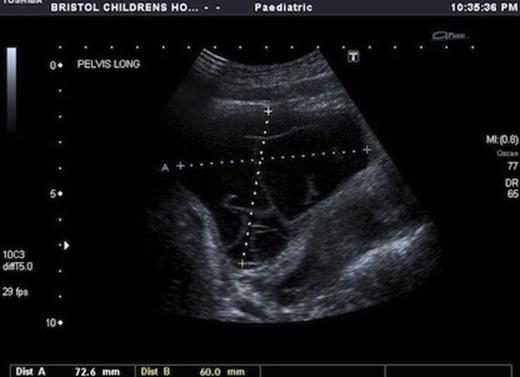

USS showed a septated cystic structure behind the bladder and abutting the ovary. There was echogenic fluid within the cysts. (Fig 1&2)

Accurate preoperative diagnosis can be difficult. Ultrasound has been used as the first line for diagnosis. It shows a wide range of findings (8), but the majority are simple cysts. Multilocular cysts, as in our case are very rare accounting for only 4% of the cases (8). Occasionally a normal ovary abutting a cyst gives a clue to the origin of these cysts but accurate pre op diagnosis remains rare.